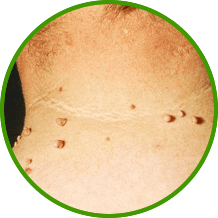

A papillómák és a szemölcsök - túlnyomórészt jóindulatú, gyakran vírusos eredetű bőrdaganatok. Csomók vagy papillák formájában jelennek meg. A humán papillomavírus (HPV) okozza. Melanómává, gyógyíthatatlan bőrrákká alakulhatnak át.

- a bőr vagy nyálkahártya jóindulatú daganata,

mely a felszín alatt, kiálló formában van jelen

- túlnyomórészt jóindulatú bőrdaganatok,

gyakran etiológiai vírus, amely csomó vagy papilla formájában jelenik meg

- durva bőrfelület, amely a felszínen kidudorodik,

melynek közepén található a gyökere (szára)

- szemölcsök, melyet a humán papillomavírus (HPV) okoz

amelyek a talpon vagy a lábujjakon jelennek meg